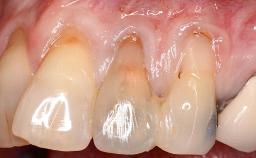

A 30-year-old woman was referred by her general dentist for evaluation of an esthetic complication related to previous implant treatment for congenitally missing maxillary lateral incisors. The patient’s chief complaint was the inadequate esthetic appearance of her smile. The case demonstrates the use of a combined approach to achieve optimal results. Two different flap designs - a tunnel technique and a coronally advanced flap - are employed based on the surgical objectives for the affected site.

Soft Tissue Anatomy Intact Defective